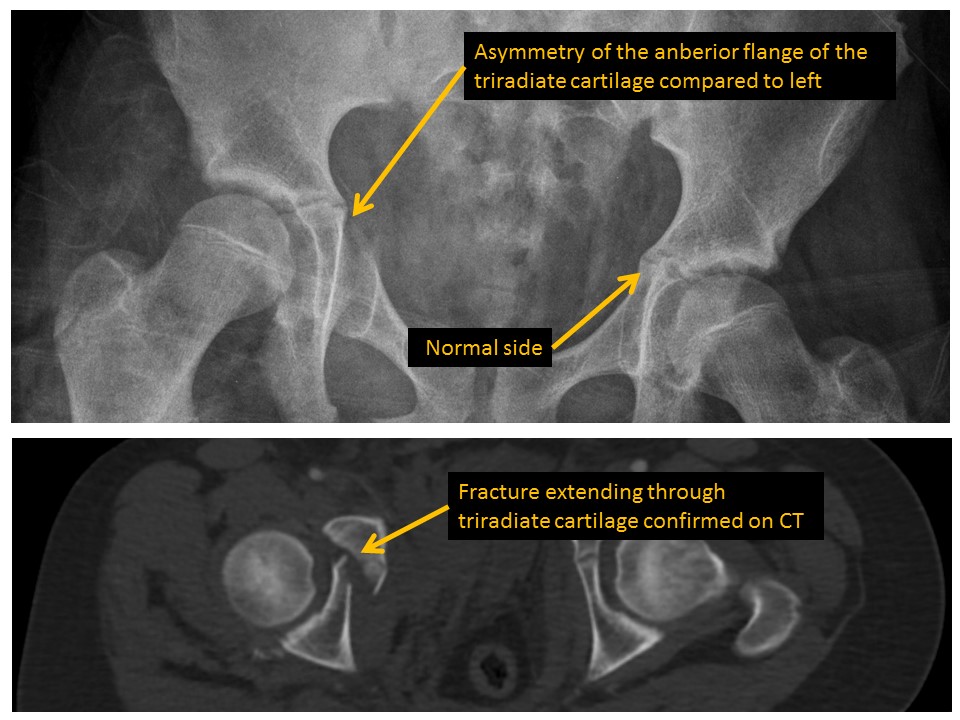

Triradiate cartilages are asymmetric. [Yes/No]

Acetabular fractures are present. [Yes/No]